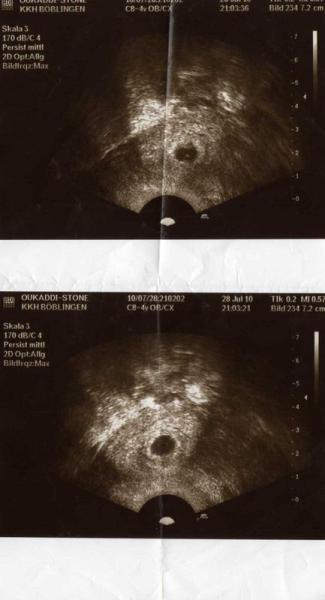

ich und mein mann haben es jetzt fast zwei jahre versucht ein kind zu erzeugen..seit dem 27.07.10 um 21:03:21 habe ich erfahren das ich schwanger bin.. ich habe mich sowas von

ich war in notfall ambulanz und durfte das us-bild mitnehmen..

schön, genauso sah mein erstes US-Bild auch aus